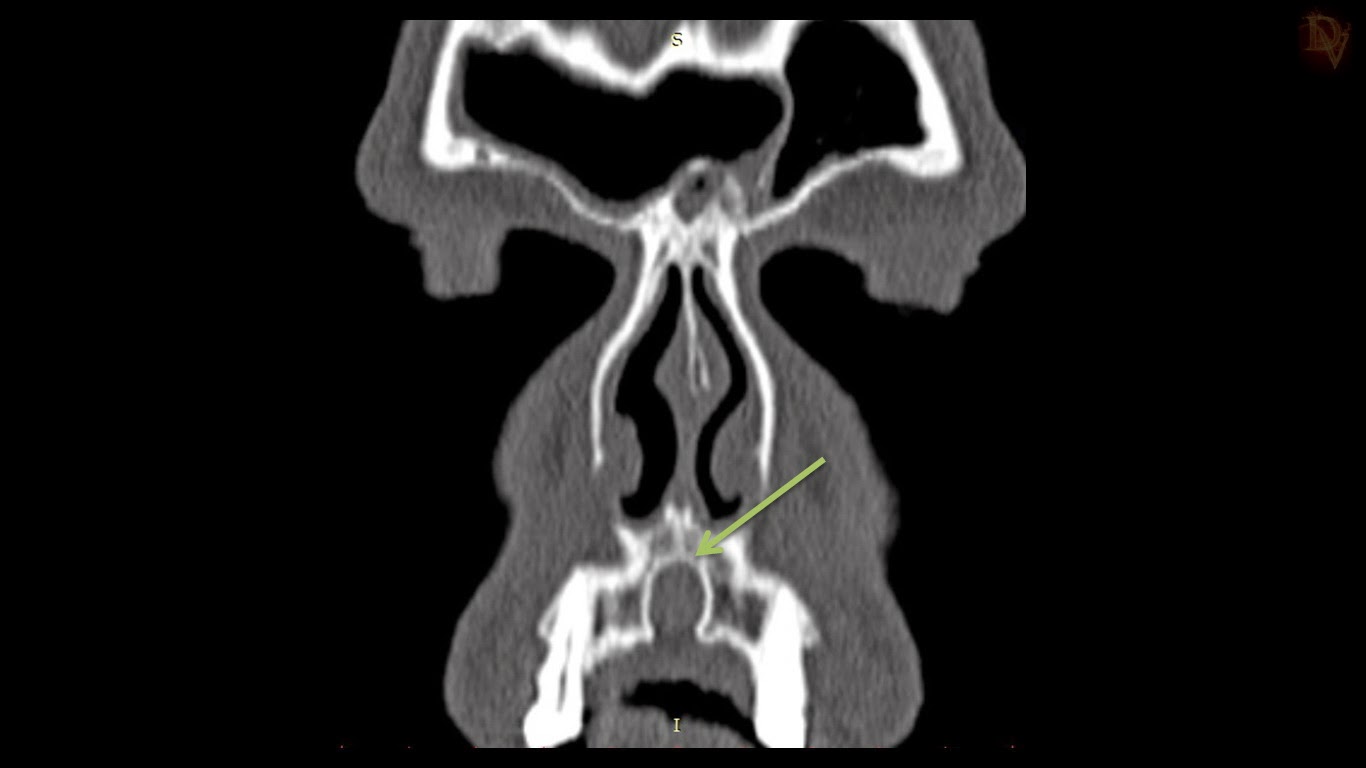

From radiopaedia.org

Nasopalatine duct cyst Image Incisive Canal Cyst Symptoms T he nasopalatine duct cyst (npdc), also known as the incisive canal cyst, is the most common nonodontogenic cyst of the oral. It may appear as extrabony incisive papilla cyst or intrabony lesion. It appears as either asymptomatic which is recognized on routine. Incisive canal cysts, also known as nasopalatine duct cysts (npdcs), are developmental, nonneoplastic cysts arising from degeneration.. Incisive Canal Cyst Symptoms.